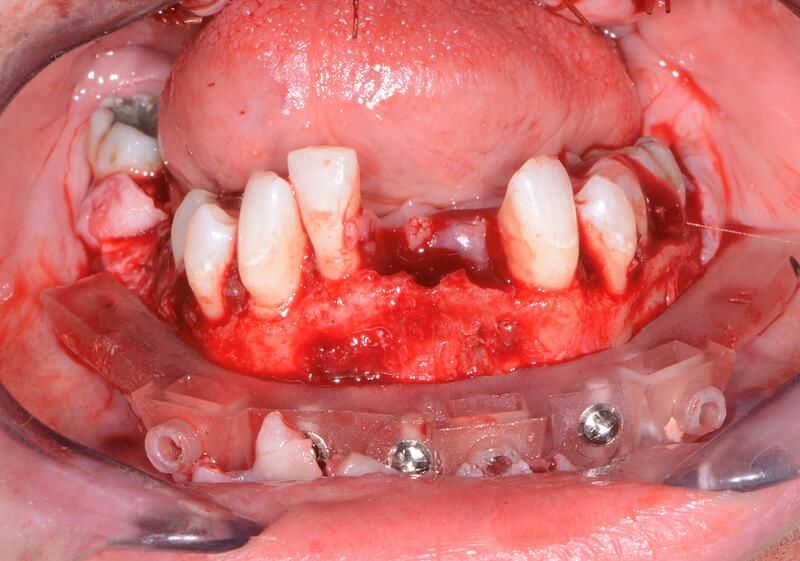

全口組合式導(dǎo)板病例

術(shù)中過(guò)程